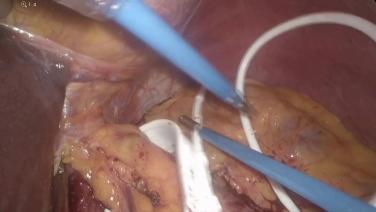

Resection of a Persistent Marginal Ulcer & Creation of a New Gastrojejunostomy